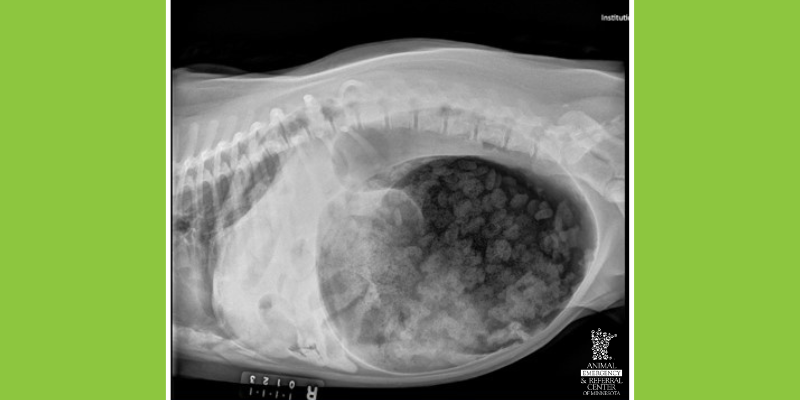

Right lateral abdominal radiograph showing Gastric Dilation & Volvulus (GDV).

5. Gastric Dilation & Volvulus (GDV)

Gastric dilation and volvulus (GDV,) also known as “bloat,” is most often seen in large breed, deep-chested dogs. Signs include pacing, non-productive retching, lethargy, and abdominal distension. In this emergency, the stomach becomes enlarged and twists on itself, preventing blood supply from getting back to the heart and sometimes leading to necrosis of the stomach.

Surgery involves de-rotating the stomach and attaching it to the body wall to prevent future twisting, a procedure known as gastropexy.